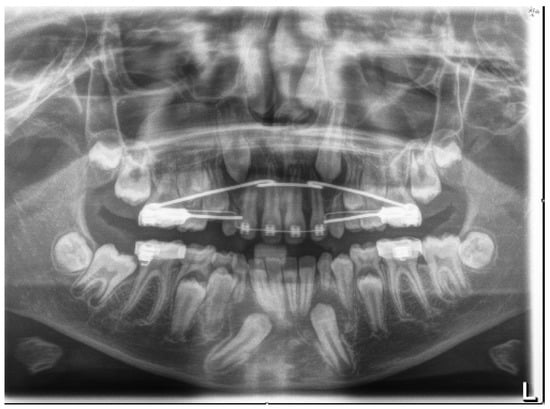

4. Case Report

4.1. Phase 1: Initial Orthodontic Treatment

4.2. Phase 2: Surgical Technique

4.3. Orthodontic Traction

4.4. Phase 3: Final Orthodontic Treatment